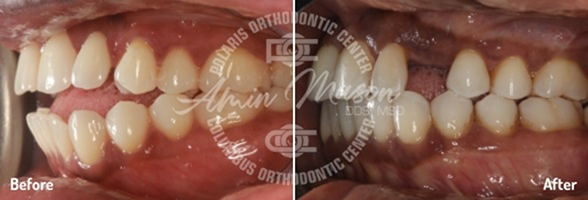

Case 3

Case 4

This 26-year-old patient wanted to straighten her severely crooked teeth because they made her feel self-conscious. Not wanting to draw any more attention to her teeth, she decided to get Invisalign. Multiple orthodontists told her that her case was too complicated for Invisalign treatment, but she persisted and eventually found Dr. Mason. He was able to combine Invisalign with a class II corrector and elastics to fully address all her issues. After going through the process, she said she was extremely happy with the results and could not stop smiling.